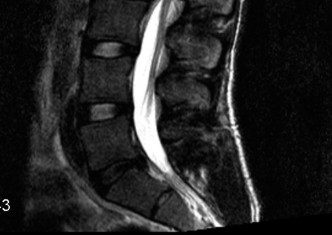

CASE 1 A 63-year-old male sustained a hyperextension injury to his neck while diving into a pool. Upon presentation, he reports decreased sensation in his hands and decreased strength in his arms and wrists, but no lower extremity complaints. On motor examination, he has 5/5 strength in his deltoids and elbow flexors and 4/5 strength in the elbow extensors, wrist extensors, and finger flexors. Lower extremity motor examination is normal. Sensation is decreased to light touch in both hands. Otherwise his sensation is preserved. Images of his cervical spine are shown in Figures 1–1 to 1–3.

Figure 1–1

The correct answer is (B). The clinical scenario describes a patient with central cord syndrome (CCS). CCS continues to be the most common incomplete spinal cord injury accounting for 15.7% to 25% of all spinal cord injuries. The characteristic presentation is an extension moment injury in a previously spondylotic and stenotic spine. Figures 1–1 to 1–3 demonstrate a spondylotic spine with central narrowing and CSF effacement that is worst at the C3–4 level. Bleeding, edema, and/or Wallerian degeneration lead to damage of the lateral corticospinal tract which is the main descending motor tract in the spinal cord. The more central anatomic position of the homunculus to the upper extremities places them at greater risk than those to the lower extremities. As such, injury to the lateral corticospinal tract is characterized by upper more than lower extremity involvement and motor deficits being more pronounced than sensory deficits.